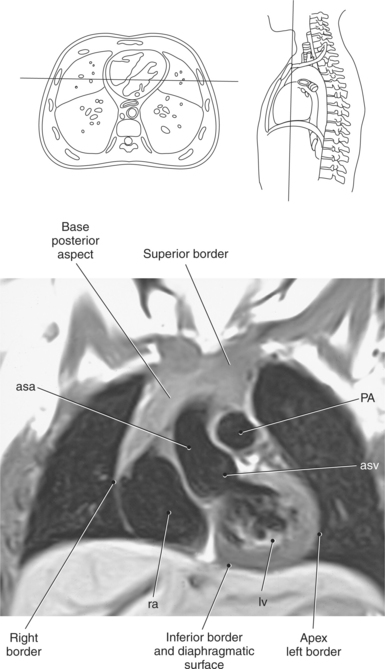

The heart is a hollow, four-chambered muscular organ located within the middle mediastinum. It is approximately the size of a large clenched fist and is situated obliquely in the chest with one third of its mass lying to the right of the median plane and two thirds to the left. The heart can be described as being roughly trapezoid shaped (Figure 6.33). The superficial relationships of the heart include the base, apex, three surfaces (sternocostal, diaphragmatic, pulmonary), and four borders (right, inferior, left, and superior). The broad base (posterior aspect) is the most superior and posterior portion of the heart. It is formed by both atria, primarily the left atrium, and gives rise to the great vessels. The apex is formed by the left ventricle and points inferiorly, anteriorly, and to the left. It is located at the level of the fifth intercostal space, just medial to the midclavicular line. The sternocostal (anterior surface) is formed primarily by the right atrium and right ventricle with a small contribution from the left ventricle. The diaphragmatic (inferior surface) rests on the central tendon of the diaphragm and is formed by both ventricles and a small portion of the right atrium. The pulmonary (left surface) is formed mainly by the left ventricle and fills the cardiac notch of the left lung. The borders of the heart represent the external surfaces of the cardiovascular silhouette in radiographic profile. The borders include the right border, formed by the right atrium and located between the superior and inferior venae cavae; the left border, formed by the apex of the heart or the left ventricle; the superior border, formed by the right and left atria; and the inferior border, which is formed primarily by the right ventricle with a small contribution from the left ventricle (Figures 6.33 through 6.35).

Figure 6.43 Axial, T1-weighted MR scan of left atrium.

Key: RV, Right ventricle; LV, left ventricle; LA, left atrium; RA, right atrium.